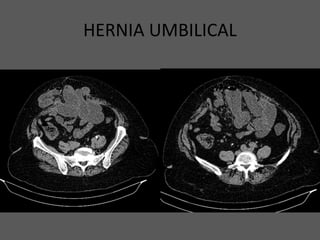

HERNIA UMBILICAL